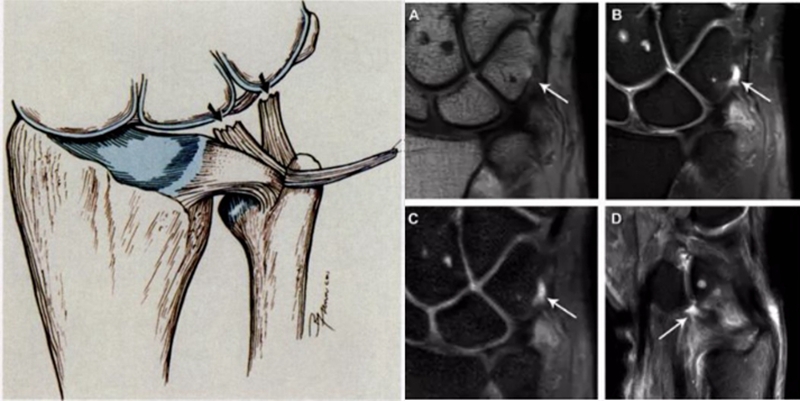

ⅠA,TFCC中心穿孔,A、B三角软骨盘正常弓形低信号缺损;C轴位显示三角软骨盘中心的高信号区与D关节镜一致

ⅠB,TFCC尺侧撕裂;TFC尺侧附着处信号增高

ⅠC,尺三角韧带撕裂

ⅠD,TFC桡侧撕裂,桡侧附着处及桡尺关节处信号增高

ⅡA,TFC局部变薄,但结构完整

ⅡB,TFC局部变薄,但结构完整,月骨软骨厚薄不均

ⅡC,TFC中心撕裂,月骨软化,月三角韧带完整

ⅡD,TFC中心撕裂,月骨软化,月三角韧带缺如

图30 ⅡE,TFC中心撕裂,月骨、尺骨软骨软化,月三角韧带缺如,桡尺关节骨质增生